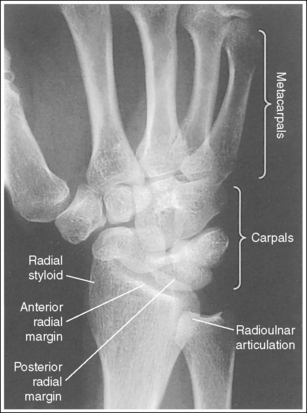

See Figure 4-29 and Box 4-11.

Contrast and density are adequate to demonstrate the scaphoid fat stripe.

• Significance of the scaphoid fat stripe. The scaphoid fat stripe is one of the soft tissue structures that should be visible on all PA wrist projections (Figure 4-30). It is convex and located just lateral to the scaphoid in an uninjured wrist. A change in the convexity of this stripe may indicate to the reviewer the presence of joint effusion or of a radial side fracture of the scaphoid, radial styloid process, or proximal first metacarpal.

The wrist is positioned in a PA projection. The radial and ulnar styloids are at the extreme lateral and medial edges, respectively, of each bone. The radioulnar articulation is open, and superimposition of the metacarpal bases is limited.

• Rotation of the wrist and forearm is controlled by the position of the hand, elbow, and humerus. A PA projection is accomplished by abducting the humerus until it is positioned parallel with the IR and the elbow is in a lateral projection. The hand is then pronated, placing the wrist in a PA projection (Figure 4-31).

• Detecting wrist rotation and radial styloid position. When the hand and wrist are rotated externally into an externally rotated PA oblique projection, the carpal bones and metacarpal bases located on the medial aspect of the wrist are superimposed, whereas those located laterally are not. The lateral interconnecting carpal and metacarpal joint spaces are also demonstrated (see Image 31). Internal rotation of the hand and wrist causes the laterally located carpal bones and metacarpal bases to be superimposed and increases visibility of the pisiform and hamate hook (see Image 32).

Image 31

Image 32

• External and internal hand and wrist rotation also cause the radial styloid to rotate out of profile and closes the radioulnar articulation.

The distal radius is demonstrated without foreshortening. The anterior and posterior articulating margins of the radius are nearly superimposed.

• The distal radial carpal articular surface is concave and slants approximately 11 degrees from posterior to anterior. Because the forearm is positioned parallel with the IR for a PA wrist projection, the slant of the distal radius causes the posterior radial margin to project slightly (0.25 inch or 0.6 cm) distal to the anterior radial margin, obscuring the radiocarpal joints.

• Distal radius superimposition: A PA wrist projection that demonstrates an excessive amount of the radial articulating surface, or if open radioscaphoid and radiolunate joint spaces are desired, view the distal radioulnar articulation to determine the correcting movement. The posterior edge of this surface is blunt, whereas the anterior edge is rounded. Study the distal end of a radial skeletal bone to familiarize yourself better with this difference. If a PA wrist projection is obtained that demonstrates the posterior radial margin distal to the anterior margin, the proximal forearm was elevated higher than the distal forearm (see Images 31 and 33). It should also be noted that when the wrist is medially rotated, the posterior radial surface is superimposed over the ulna. If the anterior radial margin is demonstrated distal to the posterior margin, the proximal forearm was positioned lower than the distal forearm. To superimpose the distal radial margins and to demonstrate radioscaphoid and radiolunate joints as open spaces (see Image 32), the proximal aspect of the forearm should be positioned slightly lower (5 to 6 degrees from horizontal) than the distal forearm.